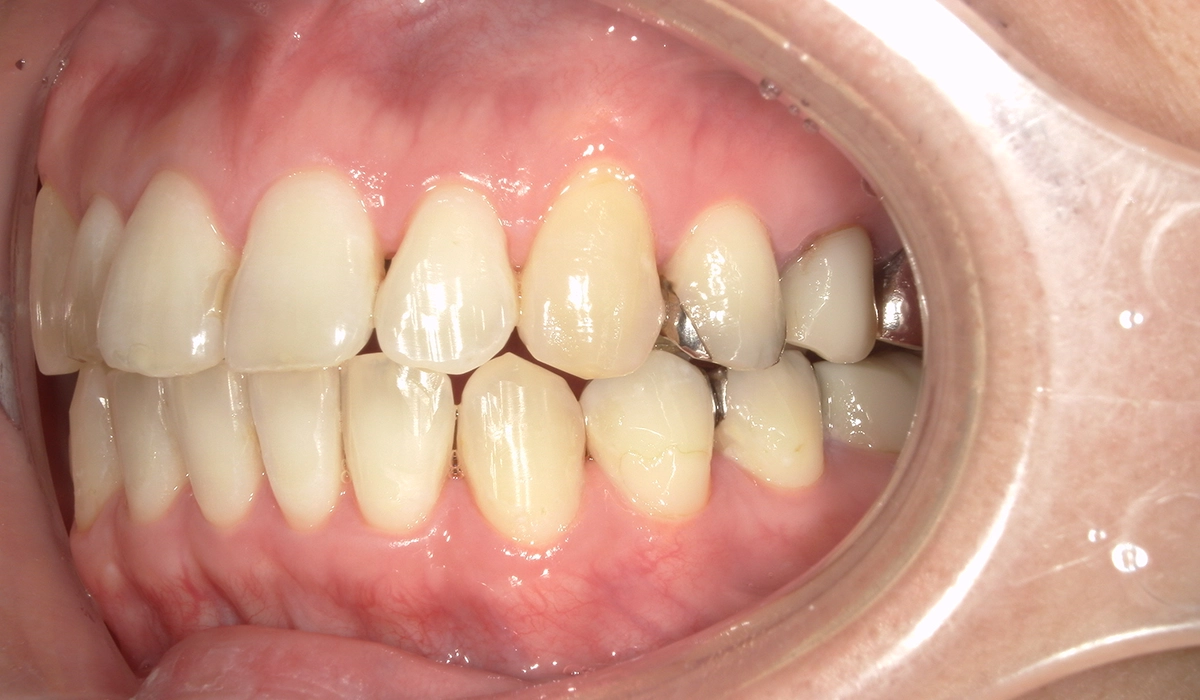

術前:右側

術後:右側